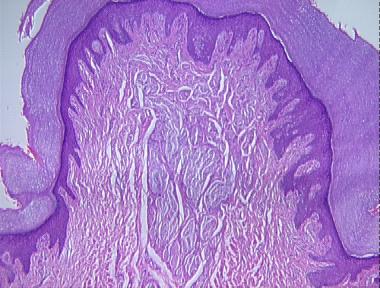

supernumerary digit with amputated neuroma

Histologic Features